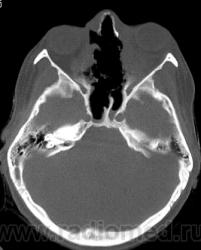

Просьба высказать мнения по поводу представленного патологического процесса.

Кажется, это уже было - гранулематоз Вегенера, если не ошибаюсь.

Гранулематоз Вегенера

Деструктивный процесс в полости носа и в пазухах может представлять собой гранулематоз Вегенера. Требуется тщательное собрание анамнеза, учет клинической картины, и разумеется, биопсия.